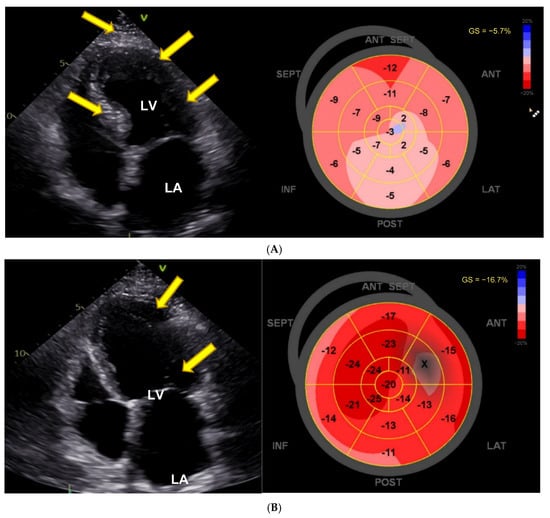

There was normal systolic and diastolic function, normal renin, aldosterone, adrenalin, and noradrenaline levels measured in serum, methoxytyramine was massively elevated (309 nmol/mL, normal range 0.59–4.19), and MRI showed no kidney or adrenal abnormalities. Echocardiography revealed signs of apical hypertrophic cardiomyopathy and decrease in global longitudinal strain (GLS) to −15.9% (Figure 1A). VEN serum concentration was not determined. VEN-associated CTOX was suspected and her migraine treatment switched from VEN to fremanezumab. Subsequently, within one year, the patient showed almost normal blood pressure values, normalization of ECG changes, and an increase in GLS to −21%. The echocardiographic signs of left ventricular hypertrophy had regressed (Figure 1B), and blood pressure had decreased to 143/84 mmHg. She had no dyspnea anymore, and her methoxytyramine levels had completely normalized.

Figure 1.

Pronounced cardiac anomaly showing features of hypertrophic cardiomyopathy. (A) Echocardiographic changes with apical hypertrophy and apical sparing pattern with decrease in strain in basal segments (white arrows). LA = left atrium, LV = left ventricle, RA = right atrium; white arrow points to left ventricular hypertrophy. Average GLS as shown on the right side is diminished and shows apical sparing (white arrows). (B) Reversal of left ventricular hypertrophy and apical sparing pattern after dose reduction of venlafaxine. LA = left atrium, LV = left ventricle, RA = right atrium; yellow arrow points to left ventricular hypertrophy. Average GLS as shown on the right side has now almost completely normalized (−21.9%), with some remaining decrease in basal septal, anteroseptal, and anterior segments (white arrows).